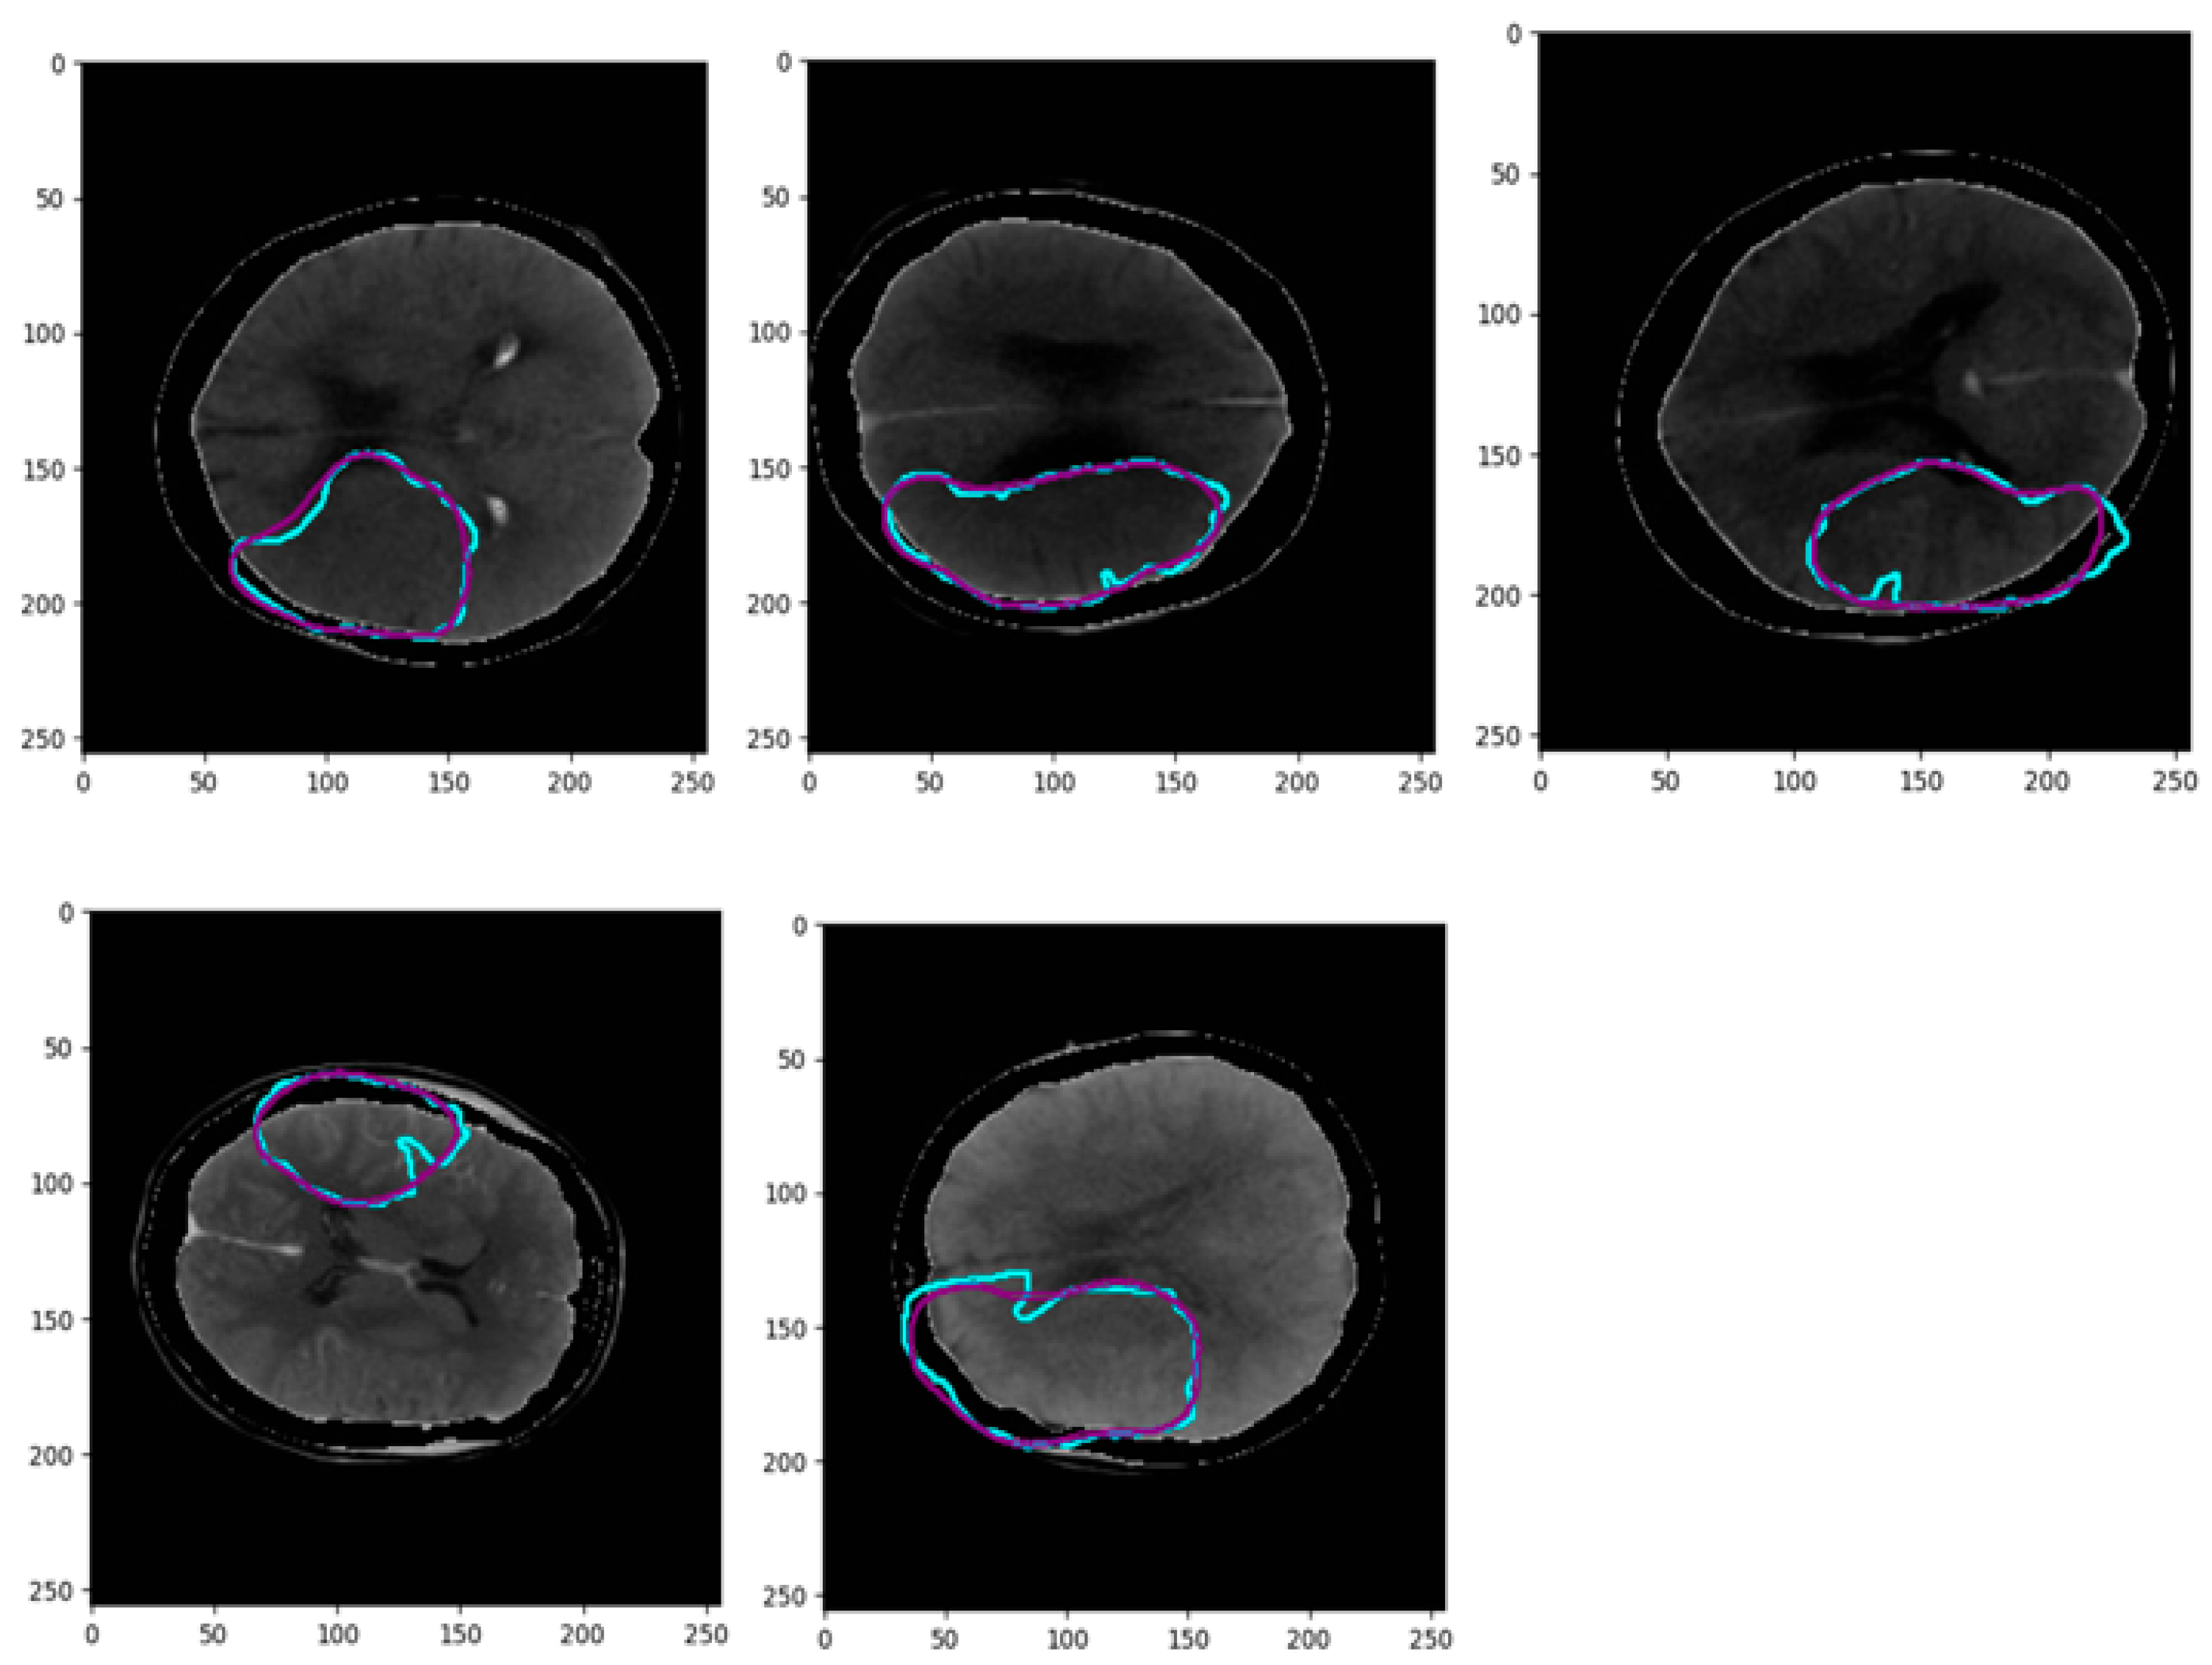

- The proposed network utilizes a channel of perfusion maps, including CBV, CBF, MTT, Tmax, and CT slice, to efficiently extract the stroke lesion.

3.1. Pre-Processing of Data

| [CBV, CBF, MTT, Tmax, CTSlice] | MultiresUNet | 76.52 | 73.09 | 75.12 | 71.19 |

| Ensemble Net | 86.61 | 84.13 | 84.98 | 77.67 | |

| CS-Ensemble Net | 92.43 | 90.14 | 91.66 | 86.16 |

| 5% | [CBV, CBF, MTT, Tmax, CTSlice] | 86.69 | 85.09 | 85.41 | 81.99 |

| 20% | 90.03 | 87.77 | 88.02 | 86.35 | |

| 80% | 92.43 | 91.30 | 91.83 | 87.82 |